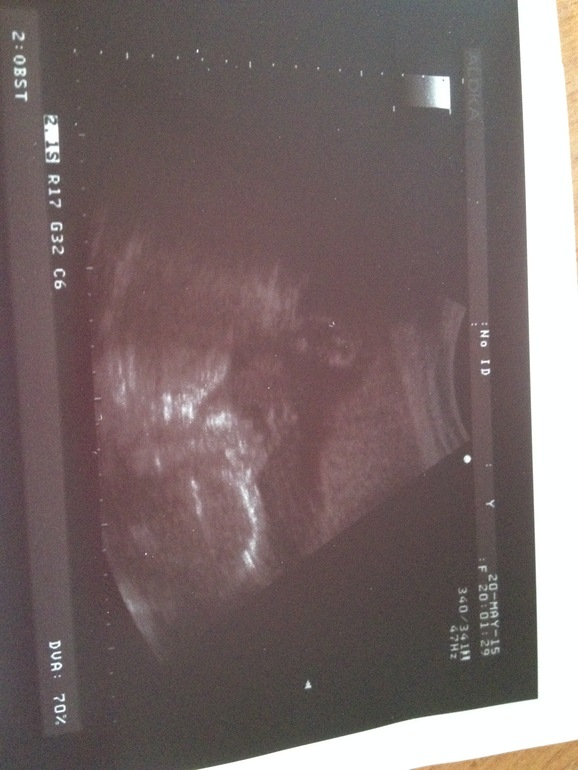

Через неделю пойду в обычный отпуск,который плавно перетечет в декрет. Не представляю.как жить на одну зп. страшновато) Кроватка уже есть.одежки на первые пол года наверное гора от племяшки, половина новая,не успели поносить) Ходили на днях на узи, досмотреть сердечко, т.к. в прошлый раз не дала посмотреть. Все в порядке, от сердца отлегло. А еще сделали фото нашей козявочки. Спала на узи) Сказали, похожа на папу. После каждого приема пищи клонит в сон и стала немного рассеяна. С одной стороны кипит энергия и хочется много всего сделать, с другой, если поработаю физически как раньше - начинает болеть спина и живот потягивать,боюсь,поэтому нагрузки свела к минимуму. Перстукиваюсь с дочей периодически,она такая активная вечером.